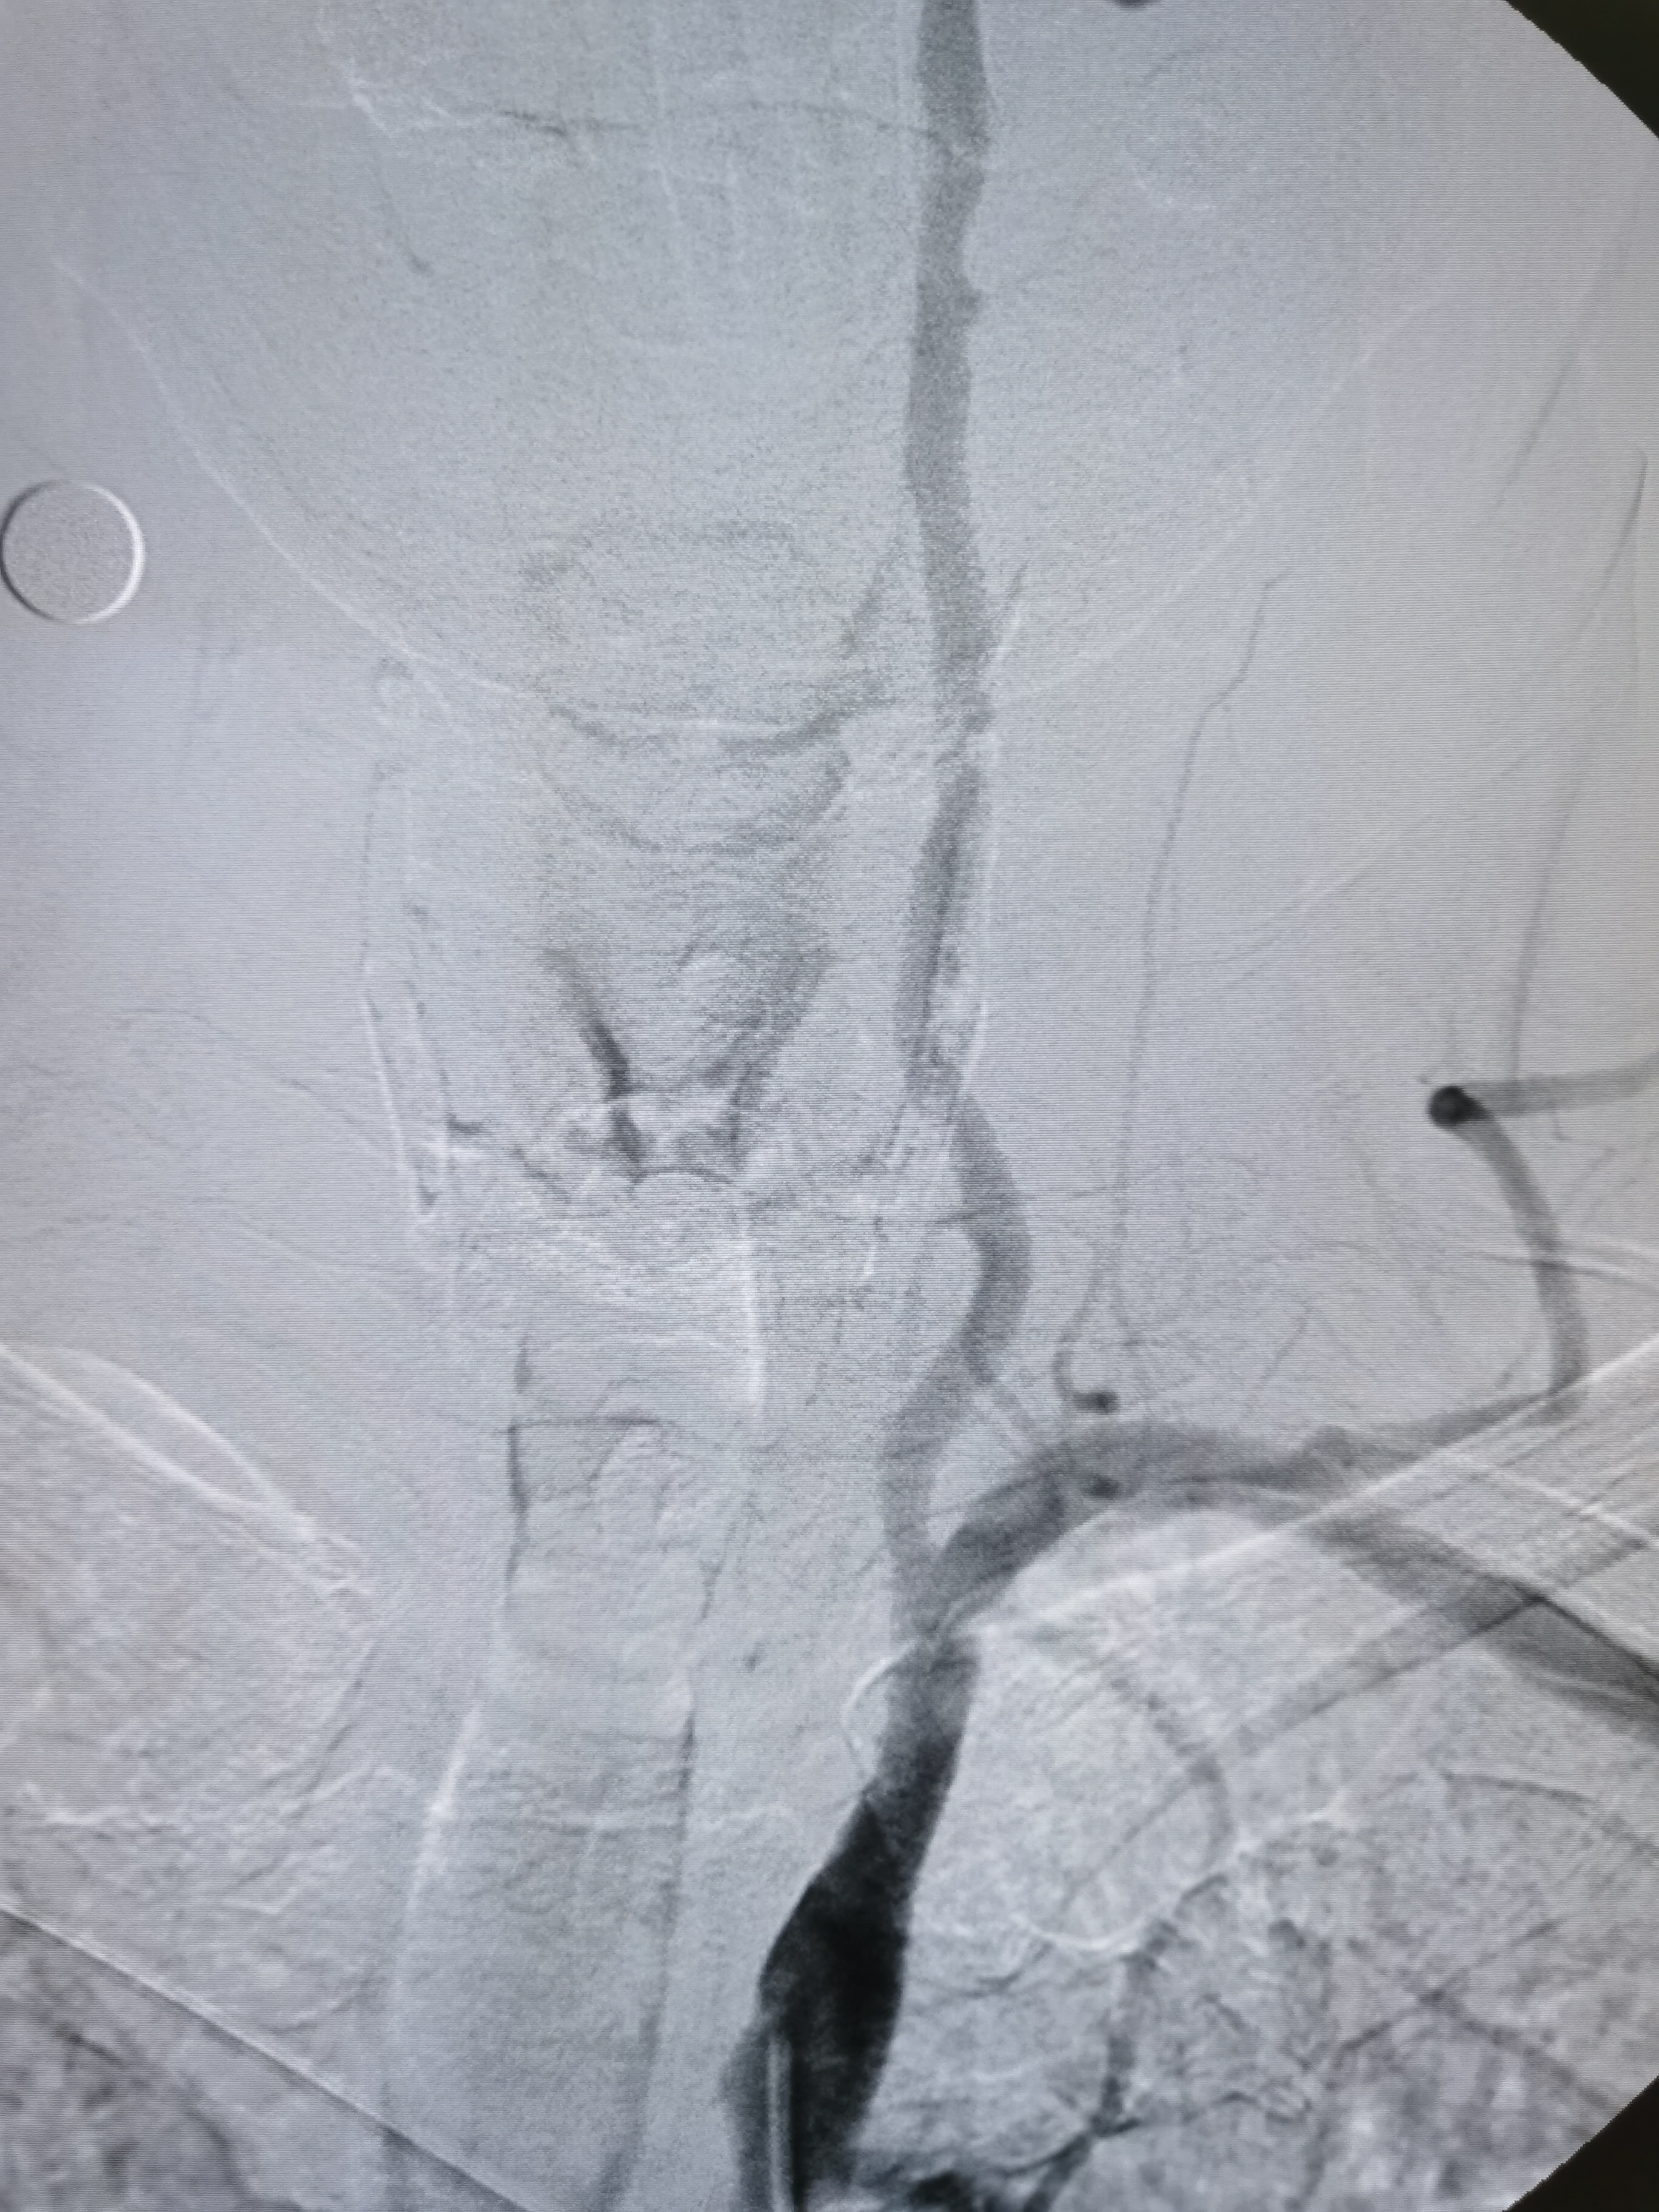

右侧颈内动脉起始部重度狭窄。

颅内段显影可。

8F导引导管到位右侧颈总动脉末端,明确狭窄。